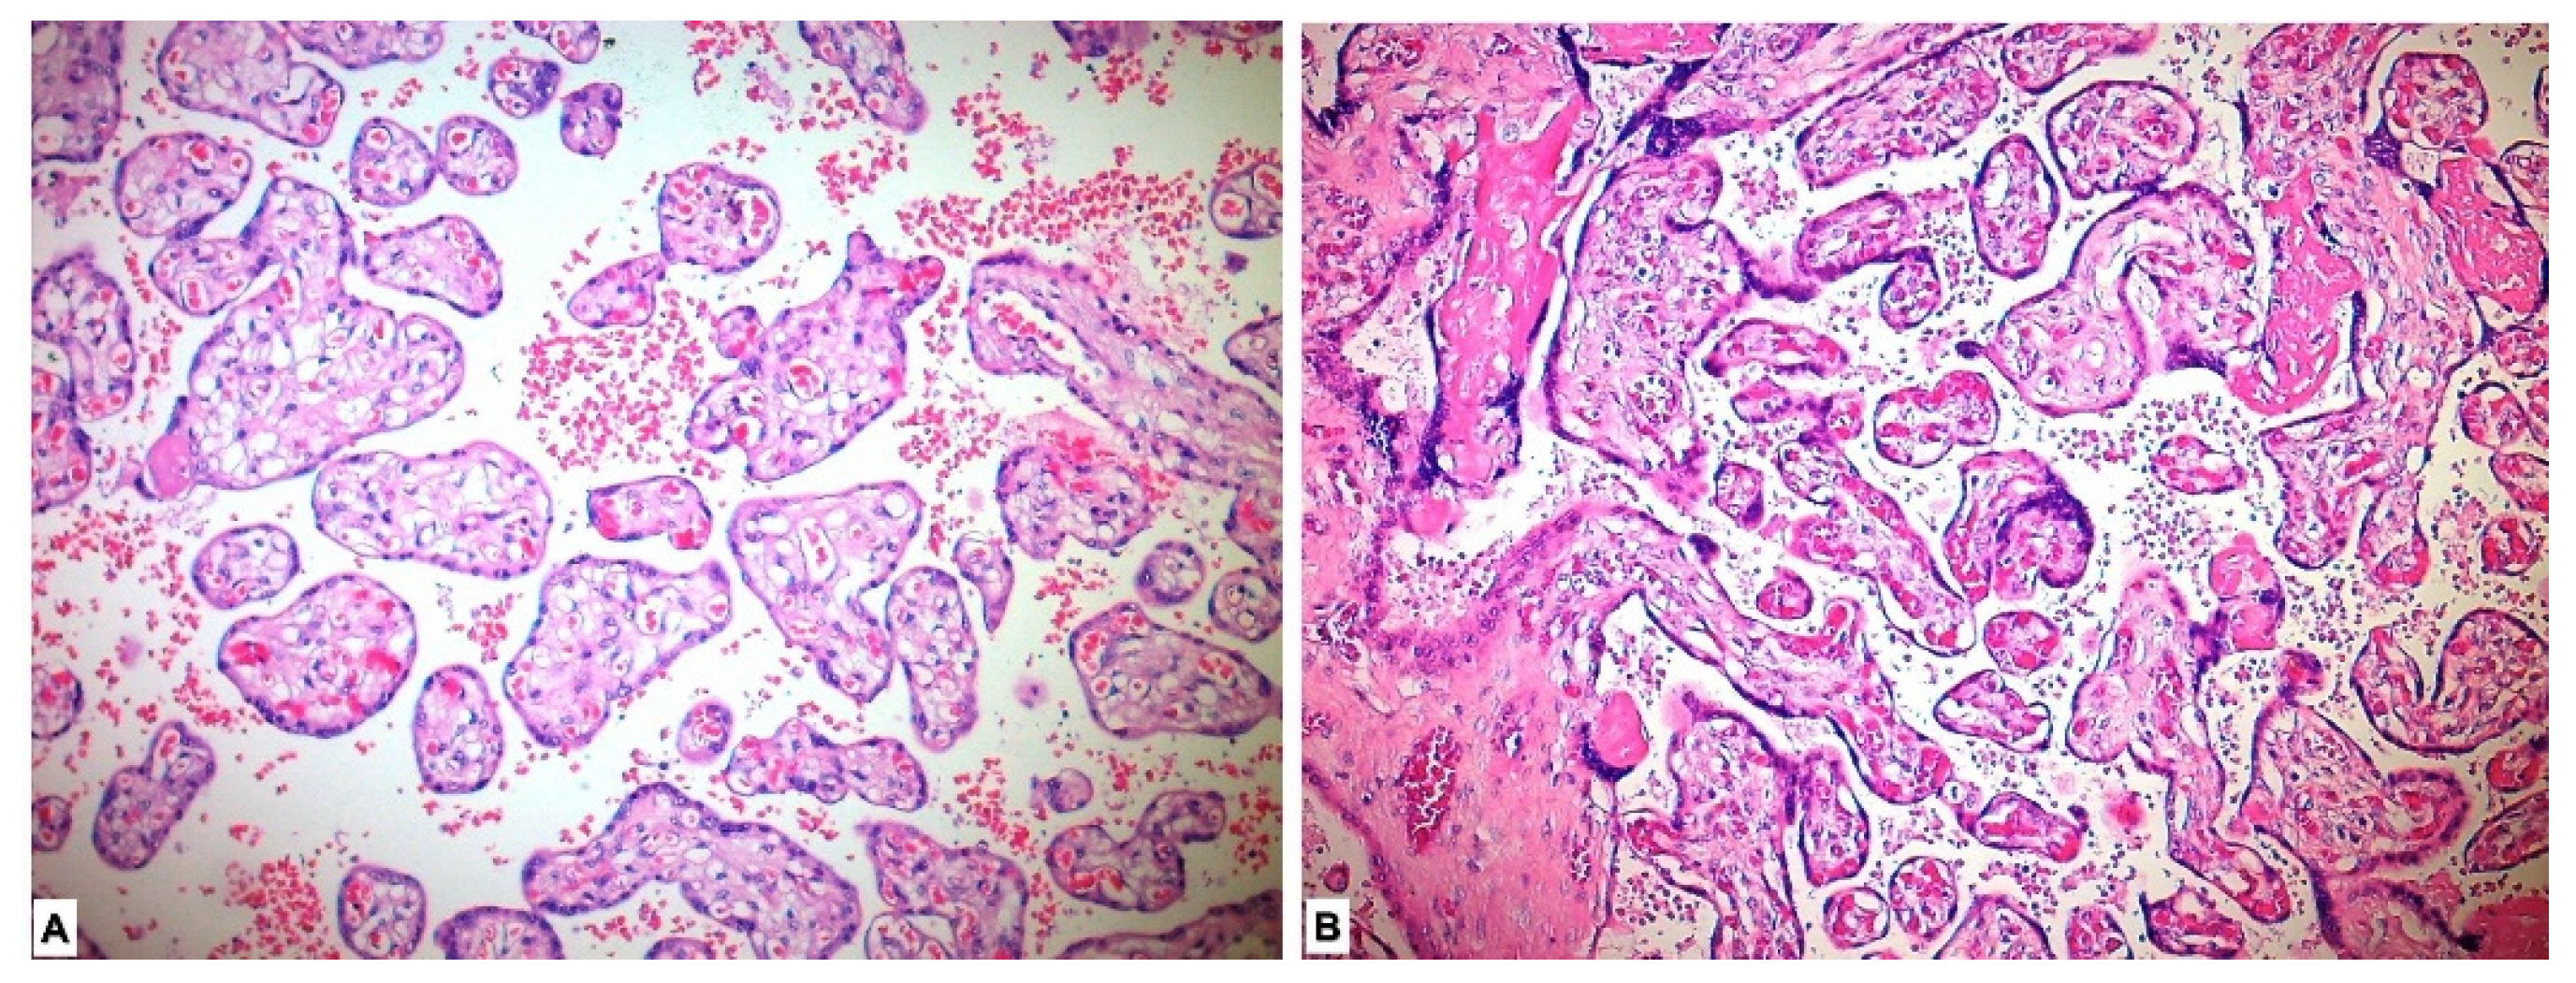

Placental pathological changes and histopathological findings were evaluated in our study. Placentas of five patients could not be histopathologically evaluated due to lack of proper staining. Deciduitis, perivillous fibrin accumulation, intervillous fibrin, intervillous hemorrhage, infarcts, calcification, laminar necrosis and syncytial node were found to be significantly more common in the study group placentas compared with those in the control group (p < 0.001) (Table 2, Figure 1).

Figure 1.

Histopathological view of placental tissues in hematoxylin-eosin sections. (A) Normal-appearing chorion villous structures in the placenta in the control group. (B) Histopathological changes showing maternal hypoxia such as perivillous-intervillous fibrin deposition and syncytial node in placental tissues of preeclamptic pregnancy.